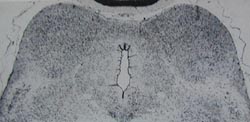

Windle (1969) and Myers (1972) found that a brief

period of total asphyxia at birth selectively damages

the inferior colliculus in monkeys [1, 2]. Figure xx in

chapter 8 is from the article by Windle and shows the

damage caused by asphyxia compared to the

appearance of the inferior colliculus in a normal

monkey. Damage to the inferior colliculus has also

been observed in human infants who died at birth.

Damage found in the inferior colliculi in monkeys subjected to sudden, catastrophic asphyxia - inflicted by delivering the head of infant monkeys into a saline-filled sac, and clamping the umbilical cord. Compare with the appearance of the inferior colliculi in a monkey born normally.

These pictures were published in the October 1969 issue of the Scientific American as part of an article by William Windle on asphyxia at birth. They were first published in the article by Ranck & Windle (1959).